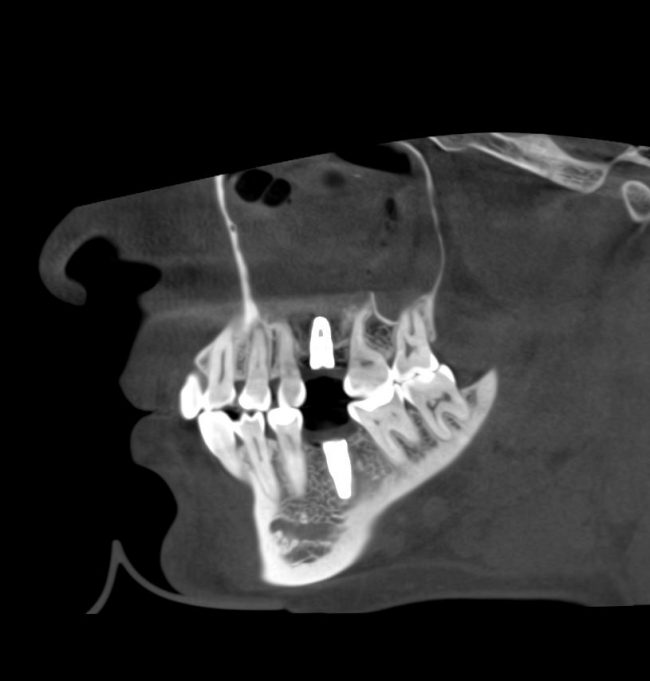

Через 3 месяца — вторая операция — установка имплантата в сформированный объем костной ткани:

Как видите. восстанавливается всё очень легко, никаких дефектов не остаётся, но при этом мы получаем важное преимущество: достаточную свободу движений при формировании субантральной полости и хороший визуальный контроль за состоянием слизистой оболочки. Никакая нажопная оптика или суперпупермикроскоп, к сожалению, не обеспечат подобный контроль при закрытом синуслифтинге. Да, операция получается травматичнее и масштабнее, чем «закрытый» синуслифтинг, но несёт в себе гораздо меньше рисков.